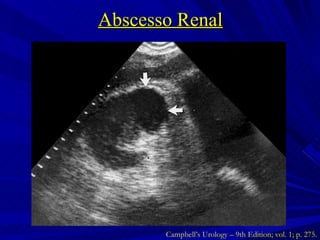

Abscesso Renal Coleção de material purulento confinado ao parênquima renal Inoculação hematogênica Gram + ( Staphylococci ) Formação no córtex renal  Infecção ascendente Gram – ( E. coli ) Formação na junção córtico-medular Campbell’s Urology – 9th Edition; vol. 1; p. 273 e 274.

Abscesso Renal Campbell’s Urology – 9th Edition; vol. 1; p. 275.

Abscesso Renal Tratamento  Abscessos < 3 cm ATB de amplo espectro direcionado à etiologia  Abscessos > 3 cm, imunodeprimidos ou falha do tratamento clínico Drenagem percutânea Campbell’s Urology – 9th Edition; vol. 1; p. 275 e 276.